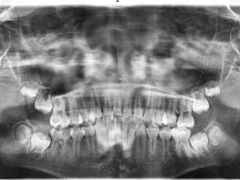

• 精德口腔·种植修复·儿牙中心(财富中心店)

• -精德口腔·种植修复·儿牙中心(财富中心店)

HOHO_8984 | 23-12-16

报错